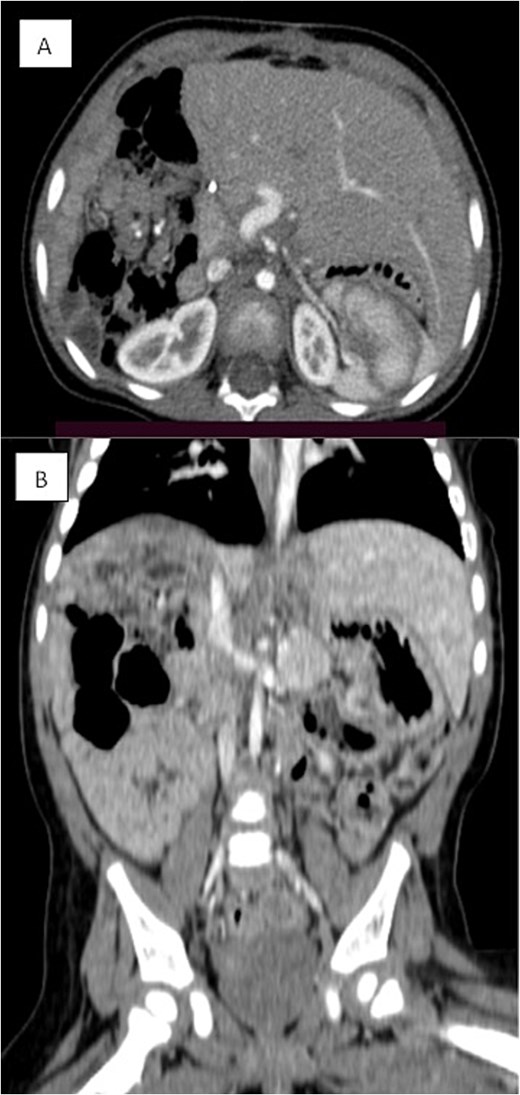

Several months later, she developed progressive abdominal distension and recurrent vomiting, prompting further evaluation. A CT scan of the abdomen revealed a large heterogeneous hepatic mass primarily occupying the right lobe, measuring 12.6 × 8.8 × 14 cm, with multicystic areas and soft tissue enhancement. MRI also demonstrated a large right hepatic lobe mass with mass effect and heterogeneous enhancement (Figs 1 and 2). Mild upper abdominal lymphadenopathy was noted (largest node 8 × 10 mm), along with a right-sided inguinal hernia. Differential diagnoses included HMH, with hepatoblastoma and undifferentiated sarcoma considered less likely. A chest CT showed mild pericardial effusion and an inflammatory appearance.

Triphasic CT examination of the abdomen post-right hepatectomy. (A) The axial view shows a clear operative bed with no residual enhancing lesions or collections. The (B) coronal view demonstrates compensatory hypertrophy and enlargement of the left hepatic lobe. Herniated bowel loops are visible, filling the right hypochondrial subphrenic region.